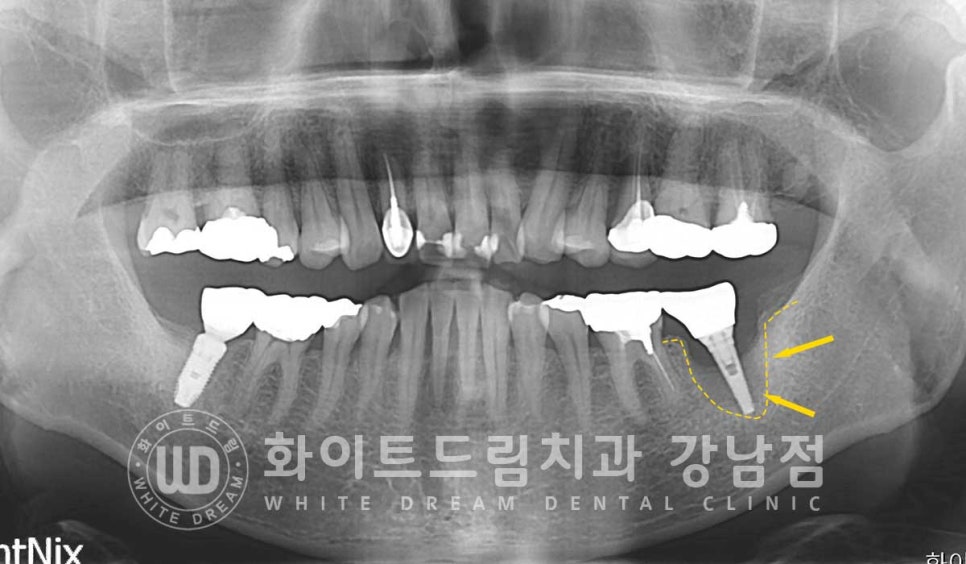

임플란트의 상태를 보니 주위 염증이 심하게 발생하고

잇몸뼈도 많이 녹아내린 상태이며 임플란트 끝부분이 잇몸뼈에 겨우 붙어 있는 상태였습니다.

환자분도 더 이상 임플란트는 사용할 수 없을 정도로

심하게 흔들리고 있는 상태라 제거 후 재식립을 진행하기로 했습니다.

오스 soi 임플란트 5.0x8.5mm 식립 후 모습니다.

(강남역 임플란트재수술 치과 / 수술일자 : 23.10.26)